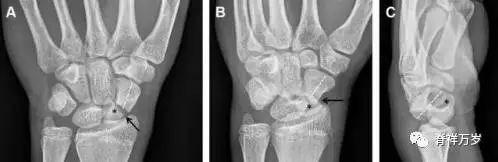

31.舟状骨骨折

舟状骨骨折 60%~70% 发生于腰部,15% 发生于近极, 10% 发生于远极, 8% 发生于远端关节面。除了常规的前后位、侧位、斜位片外,还需要拍专门的舟状骨位片(腕关节尺偏,以舟状骨为中心的腕关节前后位片),特别是鼻烟壶有压痛时。

图 2 舟状骨骨折 (A、B)第 1 例患者,舟状骨远极关节内骨折(白色箭头),斜位片显示较清楚(B);(C、D)第 2 例患者,舟状骨腰部骨折(虚线箭头),斜位片显示较清楚(D);(E~H)第 3 例患者,舟状骨近极骨折,常规 X 线片均未看到骨折,而在舟状骨位片上才能见到骨折(虚线圆)。